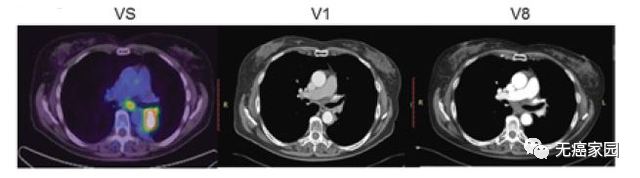

本研究中,采用局部输注 NKG2Dp CAR-NK的方式治疗了3 例转移性结直肠癌患者。前两例患者腹腔输注低剂量 CAR-NK 细胞后,可观察看腹水生成量减慢以及腹水样本中肿瘤细胞的数量急剧减少。第三例肝转移瘤患者采用超声引导下瘤内经皮注射和腹腔内灌注方式输注 CAR-NK细胞后,多普勒超声可见肝部肿瘤快速缩小,正电子发射断层扫描(PET-CT)提示经治疗的肝病灶为完全代谢反应。3 例患者在治疗过程中均无出现3级或以上的不良事件。

第3例患者多普勒超声成像显示局部注射 CAR-NK 细胞降低肝转移病灶肿瘤负荷

CAR-NK 细胞治疗后肝转移病灶 PEC-CT 结果对比图

(患者肝Ⅵ段的最大氟脱氧葡萄糖(FDG)摄取值从 8.2 降至 0.14,经评估为完全代谢缓解)

本项研究结果初步显示 NKG2D mRNA CAR-NK细胞局部输注治疗转移性结直肠癌患者具有安全性和可行性,为肿瘤免疫治疗提供了一种新的策略。